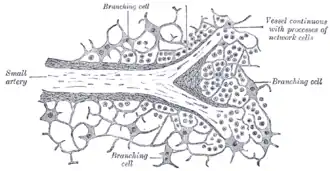

Section of the spleen, showing the termination of the small blood vessels. | |

The blood is collected from the interstices of the splenic tissue by the rootlets of the veins, which begin much in the same way as the arteries end.

The connective-tissue corpuscles of the pulp arrange themselves in rows, in such a way as to form an elongated space or sinus.

They become elongated and spindle-shaped, and overlap each other at their extremities, and thus form a sort of endothelial lining of the path or sinus, which is the radicle of a vein.

On the outer surfaces of these cells are seen delicate transverse lines or markings, which are due to minute elastic fibrils arranged in a circular manner around the sinus.

Thus the channel obtains an external investment, and gradually becomes converted into a small vein, which after a short course acquires a coat of ordinary connective tissue, lined by a layer of flattened epithelial cells which are continuous with the supporting cells of the pulp.